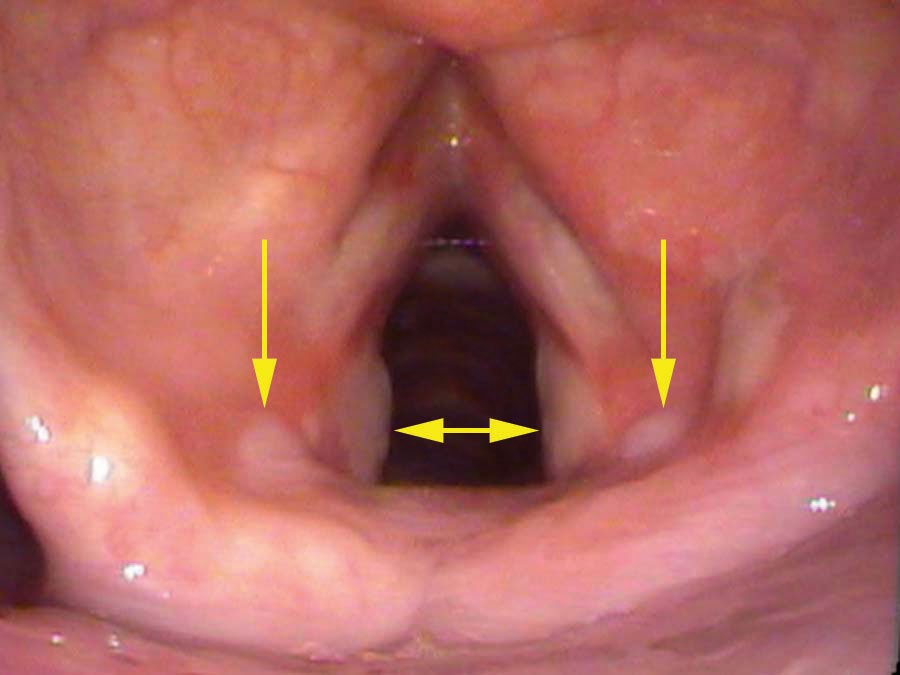

Chronic Trauma: Bowing and Compensation

Sam’s more likely cause is compensation for vocal cord bowing. His vocal cords are visibly thin — a thyroarytenoid muscle that has atrophied or is weakened causes the cord to bow. When he closes his vocal cords to speak, the bowed cords fail to seal cleanly, so he squeezes harder to compensate. That harder squeeze drives the vocal processes — small cartilage knobs at the back of the cords — into each other with greater force than normal. Over time the mucosa over the cartilage erodes and an ulcer forms; granulation tissue follows.

Other chronic trauma scenarios include: a prolonged cough (vocal processes slamming together repeatedly at high force), a severe vocal overuser who speaks aggressively and loudly, or an older patient with vocal cord atrophy requiring compensation. The shared mechanism is always the same: forceful and frequent striking of the vocal processes against each other, erosion of the overlying mucosa, and the formation of an ulcer.